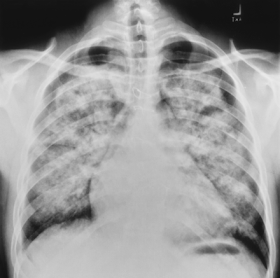

1) Pulmonary Alveolar Edema. There is extensive, bilateral airspaces disease with fluid in the minor fissure (blue arrow) and bilateral pleural effusions (ref arrows). Although the heart is not enlarged, the cause was still on a cardiogenic basis.http://www.google.com.eg/imgres?imgurl=http://www.learningradiology.com/caseofweek/caseoftheweekpix2007-1/cow267arr.jpg&imgrefurl=http://www.learningradiology.com/archives2007/COW%2520267-Pulmonary%2520edema-CHF/pulmedemacorrect.html&usg=__YRtgi0C8v73xQys3usyMs9_3_Vw=&h=443&w=500&sz=38&hl=en&start=8&sig2=GWET39uAxZAeo7LW_hF9VQ&itbs=1&tbnid=DIXYRi9W8kwI2M:&tbnh=115&tbnw=130&prev=/images%3Fq%3Dpulmonary%2Bedema%2Bx%2Bray%26hl%3Den%26sa%3DG%26gbv%3D2%26tbs%3Disch:1&ei=nHMwTNOmOMuTjAfIjbHDBQ